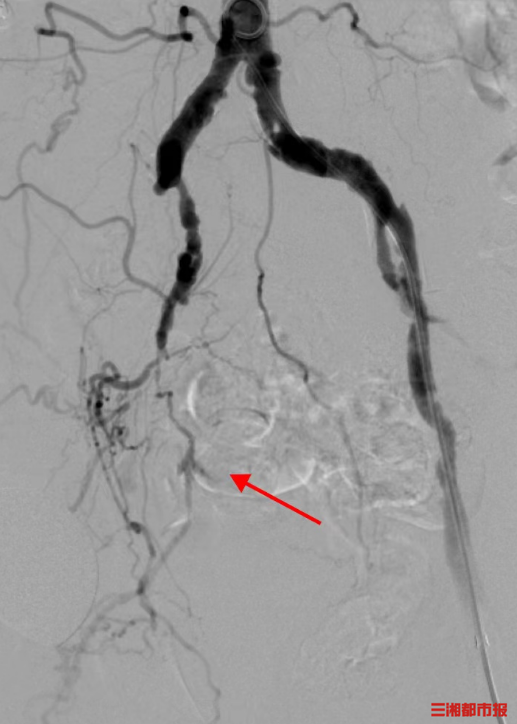

老人来到湖南省人民医院岳麓山院区介入血管外科四病区就诊,诊断为双侧髂动脉及双下肢动脉粥样硬化闭塞。如不及时开通血管,将面临截肢。医院介入血管外科团队为老人施行右下肢动脉腔内成形术,顺利开通下肢动脉, 老人右下肢疼痛减轻。

介入血管外科四病区姚袁晖副主任医师解释,下肢动脉硬化闭塞症是由于下肢动脉粥样硬化斑块形成,引起下肢动脉狭窄、闭塞,进而导致肢体慢性缺血性疾病。该病的早期症状不明显,随着病情的发展,症状由下肢发凉、麻木转变为肢体疼痛、行走间歇跛行,直到最后产生坏疽和溃疡,导致肢端坏死。